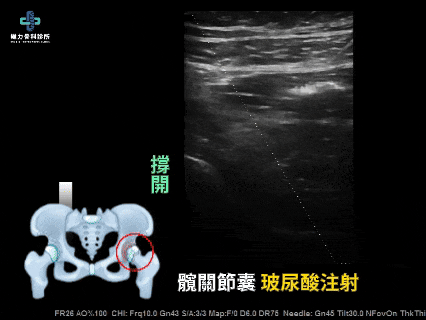

髖關節玻尿酸注射